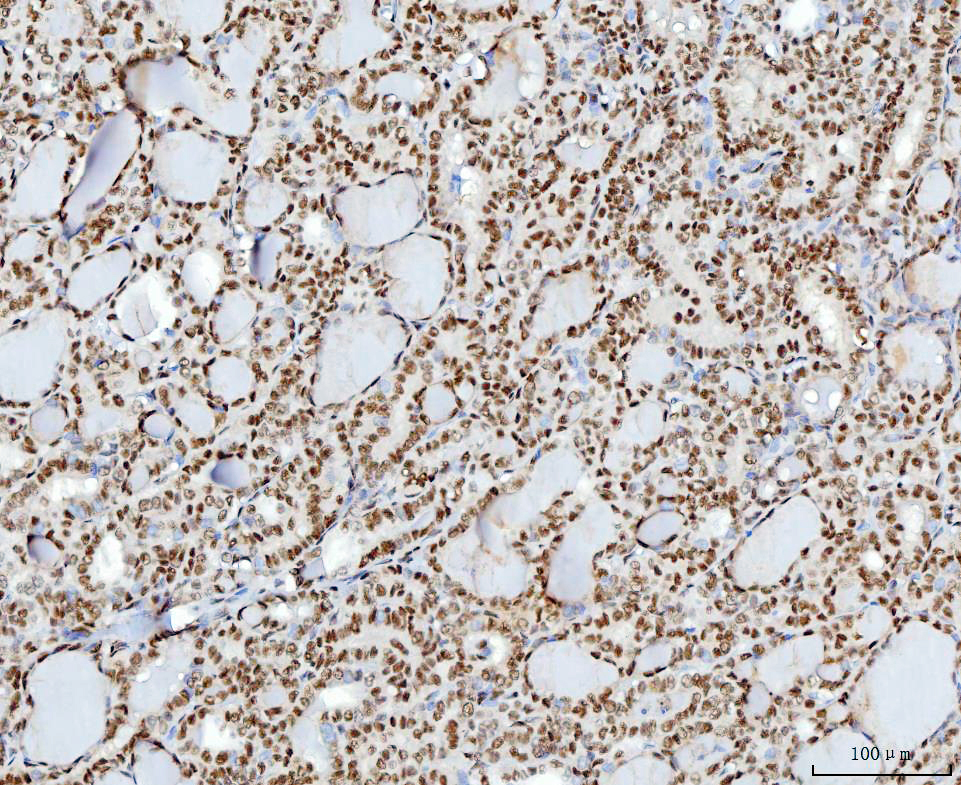

IHC analysis of YY1 using anti-YY1 antibody (M00833-3).

YY1 was detected in a paraffin-embedded section of human thyroid cancer tissue. Biotinylated goat anti-mouse IgG was used as secondary antibody. The tissue section was incubated with mouse anti-YY1 Antibody (M00833-3) at a dilution of 1:200 and developed using Strepavidin-Biotin-Complex (SABC) (Catalog # SA1021) with DAB (Catalog # AR1027) as the chromogen.